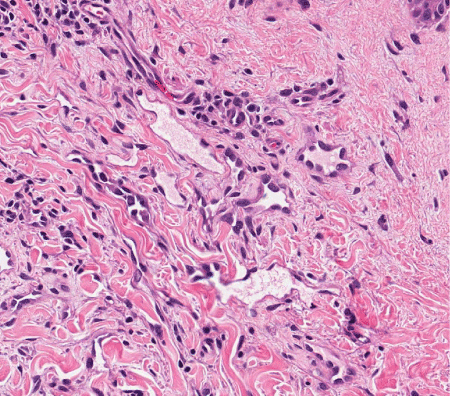

AS of the breast presents clinically as erythematous plaques or nodules, with multifocality or diffuse involvement of the breast not uncommon [13].  Histologically, AS can show heterogenous features, with well-differentiated areas mixed with or directly adjacent to poorly-differentiated components. Extension into the subcutis as well as the breast parenchyma itself is frequently observed, and various combinations of patterns (vasoformative, sievelike, kaposiform, or solid) can be present within a single tumor (Figure 1) [13]. Endothelial cell multilayering is a feature, and intraluminal blood or “blood lakes” may be present [16]. Malignant cells demonstrate prominent nucleoli, brisk mitotic activity, and an infiltrative growth pattern with prominent dissection between dermal collagen bundles (Figures 2-5) [17]. The surrounding normal tissue may show radiation-induced changes including homogenized collagen and mildly atypical dermal fibroblasts [6]. When immunohistochemistry is necessary to establish the origin of the tumor cells, CD31 is the single best marker with high sensitivity and specificity, though caution in interpretation is required as it can also stain macrophages (Figure 6) [13]. Erythroblast transformation specific related gene (ERG), a nuclear stain which is equally as sensitive but not as specific as CD31, is another useful marker that can complement the cytoplasmic/membranous staining of CD31 (Figure 7) [18]. CD34 may be negative in poorly-differentiated areas (Figure 8) [19]. Aberrant cytokeratin expression is an important pitfall, especially in epithelioid AS [13,15].

Figure 3. AS. Malignant endothelial cells encircling individual collagen bundles. H&E, 200x.